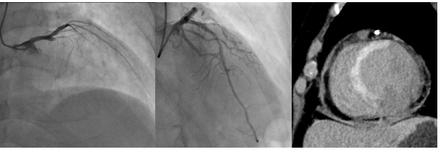

Reperfusion therapy such as percutaneous coronary intervention (PCI) is widely used in patients with acute myocardial infarction (AMI). While hemorrhagic transformation is frequently discussed in cerebral infarction following reperfusion, little attention has been given to hemorrhagic infarction in the setting of AMI. Clinically, we noticed that some patients exhibited transient ST re-elevation immediately after reperfusion, whereas others did not. This observation prompted us to investigate the potential relationship between transient ST re-elevation and the presence of myocardial hemorrhage. To this end, we performed contrast-enhanced CT scanning shortly after reperfusion therapy to evaluate myocardial bleeding.

We enrolled patients diagnosed with AMI with proximal lesions in the left anterior descending artery. A CT scan was conducted within 10 minutes of the final coronary angiography to visualize dye accumulation from the base to the apex of the left ventricle. Myocardial hemorrhage was defined based on CT density: an area more than 20 Hounsfield Units (HU) above the density of the non-infarcted myocardium and less than 400 HU, to avoid interference from stents or calcifications.

A total of 39 patients were studied. Among them, 11 exhibited transient ST re-elevation following reperfusion (re-elevation group), while the remaining 28 did not (no re-elevation group). In the re-elevation group, the dye volume index ranged from 9.38 to 25.46 ml/m2, whereas in the no re-elevation group, it ranged from 0 to 10 ml/m2. The difference was statistically significant, suggesting that re-elevation was associated with greater myocardial dye accumulation. Moreover, penetrating myocardial pigment elevation was frequently seen in the re-elevation group but was absent in the no re-elevation group.

CT imaging performed shortly after reperfusion therapy in AMI patients can help detect myocardial hemorrhage. The presence of transient ST re-elevation immediately after reperfusion may serve as a clinical indicator of myocardial hemorrhage, which tends to be transmural in such cases.